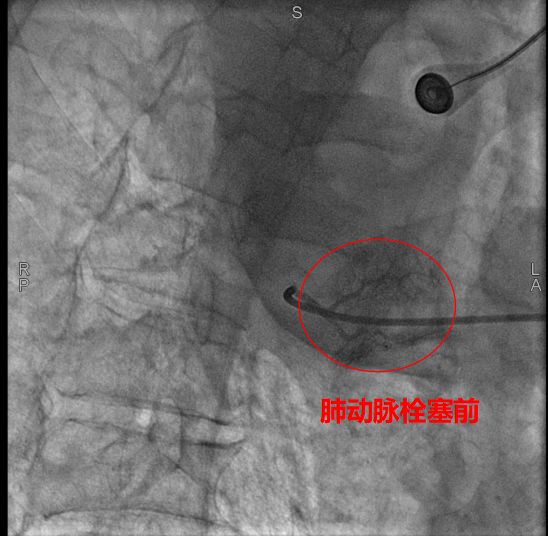

術中,數字減影血管造影(DSA)顯示患者右側支氣管動脈及胸廓內動脈增粗紊亂,末梢血管可見造影劑點狀外溢,明確為主要出血責任血管。團隊采用400?μm栓塞微球及560–710?μm明膠海綿顆粒,對出血動脈遠端實施精準栓塞,實現“末梢血管封堵”;同時,對肺動脈分支血栓相關區域也予以栓塞處理,以全面控制咯血來源。術后造影確認出血完全停止,患者安返病房后未再咯血,胸悶、氣促等癥狀顯著緩解。